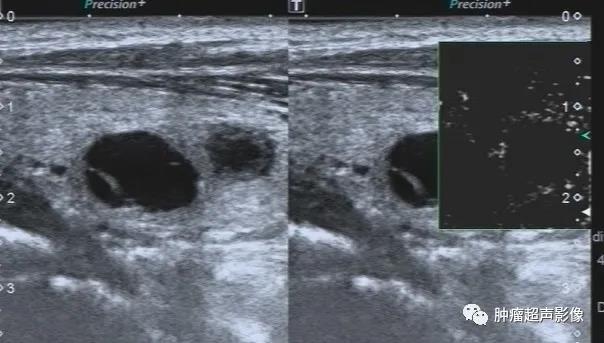

甲状腺结节呈低回声,局部边缘欠光整,内见粗钙化,可分到4类,内部无血流,

回顾以前检查可发现同一位置有一囊实性结节(下图),从而确诊皱缩结节,避免穿刺及手术。